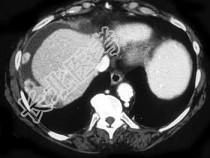

- 单项选择题女,55岁, 结合所示图像,最可能的诊断是 ( )

A、卵巢癌种植转移

B、间皮瘤

C、良性肿瘤

D、石棉沉积症

E、以上都不是